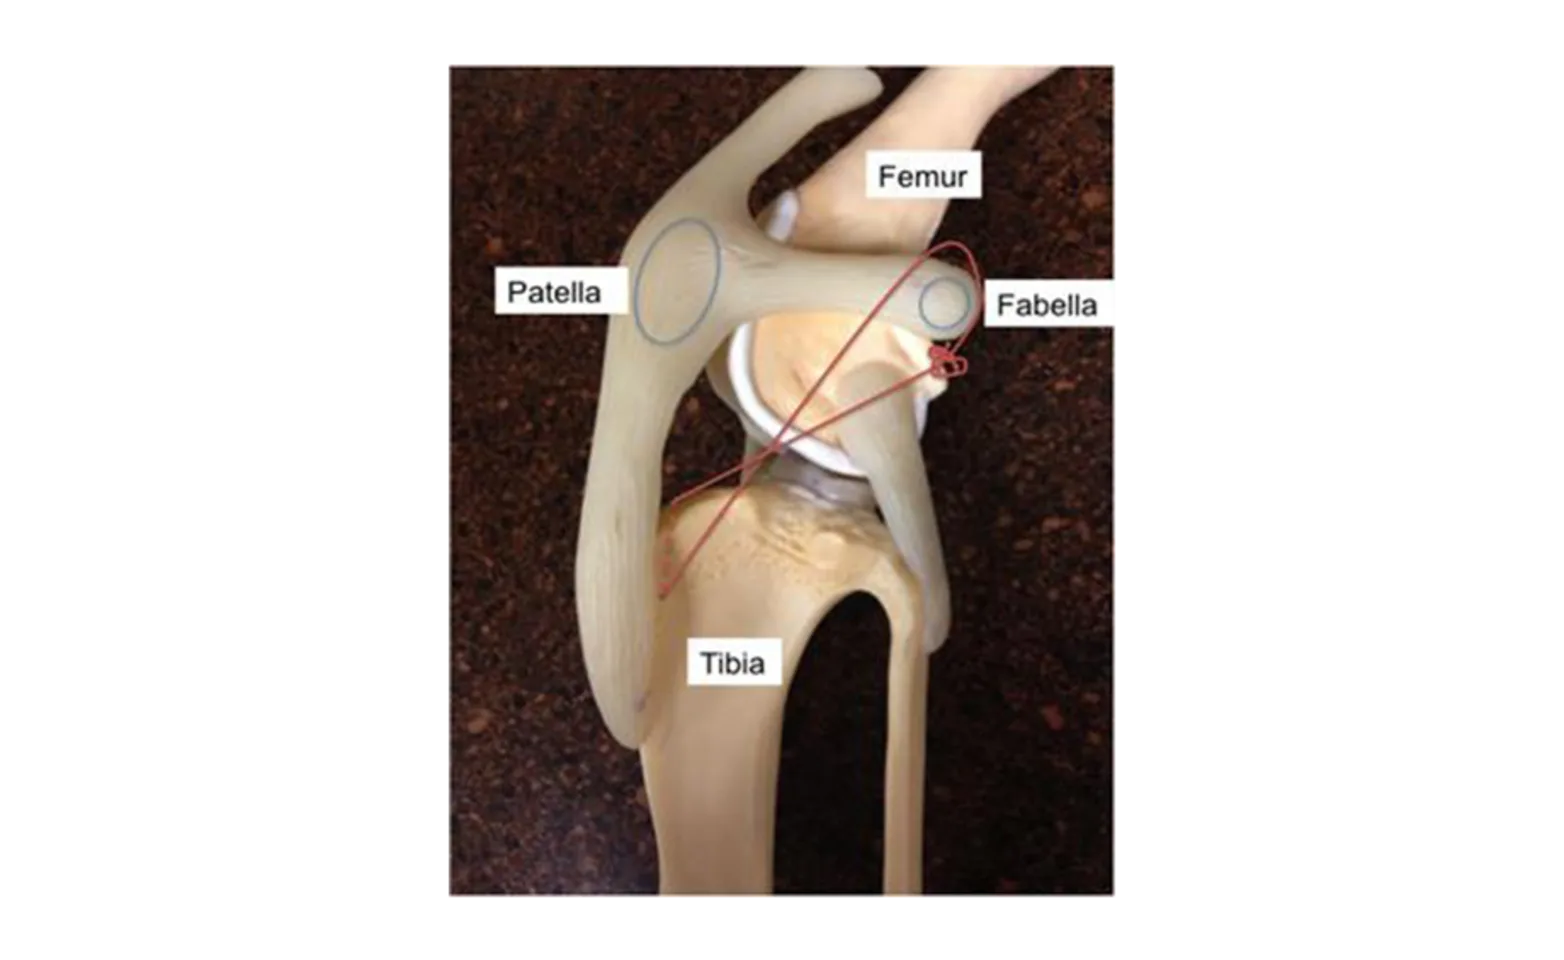

Cranial cruciate ligament (CCL) disease is the most common orthopedic disease in dogs. The CCL is located inside the knee and functions to stabilize the knee during locomotion. Because the articular surface of the canine tibia (shin bone) is sloped backward, normal locomotion leads to forward translation (tibial thrust) of the tibia in relation to the femur (thigh bone). An intact CCL will maintain the stability of the knee, but a damaged or torn CCL will lead to abnormal motion such as tibial thrust. This instability can lead to lameness, osteoarthritis, abnormal cartilage wear, and/or meniscal injury.

The TPLO is the most common orthopedic procedure performed at DVSC for dogs with CCL disease. The theory behind the TPLO is to flatten the natural slope of the tibia in order to eliminate tibial thrust and provide stability to the knee (see procedure). To the right is a picture of the stifle and associated structures mentioned above.